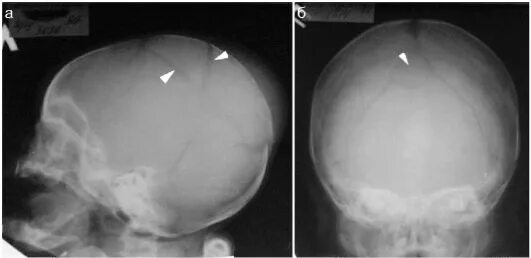

Оскольчатый перелом черепа